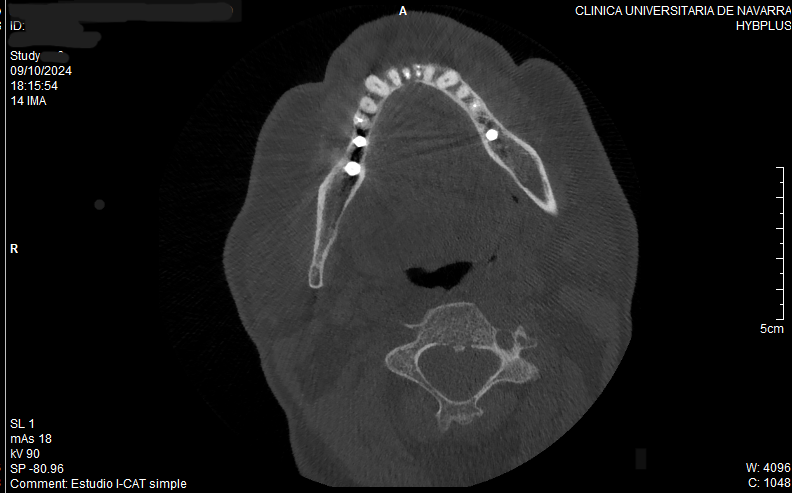

Tras realizar un diagnóstico por imagen en 3D, observamos la pérdida total de la cortical vestibular y lingual a nivel del 4.1 (Figura 7 -8).